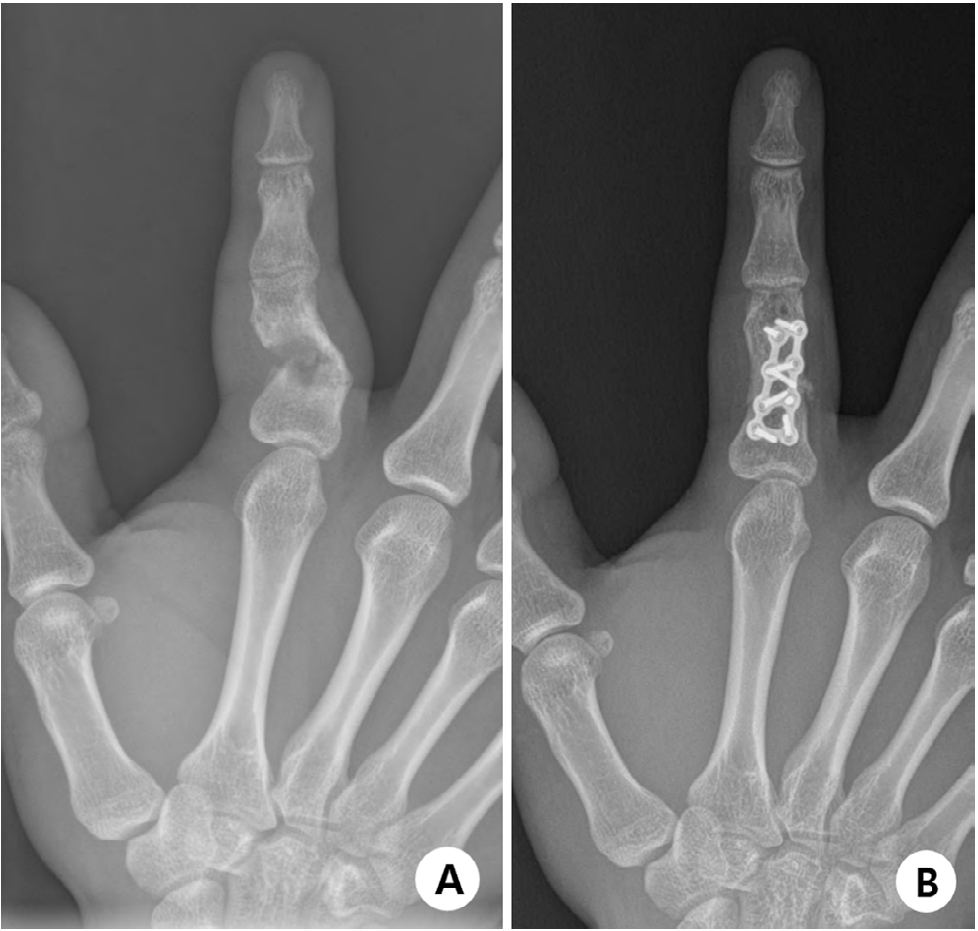

Hook plate fixation for volar plate avulsion fractures of the middle phalanges in Korea: a case series

Kang-San Lee, Sang-Woo Son, Hee-June Kim, et al.

J Musculoskelet Trauma 2026;39(1):48-53.